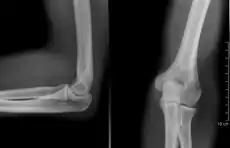

radiographie (coude droit)

Coude gauche